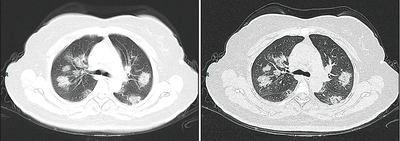

الأشعة المقطعية

Chest CT scans can sometimes help identify and characterize lung pathology, and have yielded non-specific findings with COVID-19 infection. A systematic review of chest CT scan findings in 919 patients described the typical early manifestation of COVID-19 as "bilateral multilobar ground-glass opacification (GGO) with a peripheral or posterior distribution".[133] One study found that the sensitivity of CT for COVID-19 infection was 98% compared to RT-PCR sensitivity of 71%; however, this was performed in Wuhan province of China and is not generalizable.[134] Most common CT scan findings were bilateral ground-glass attenuation (patchy or diffuse) with subpleural dominance, crazy paving and consolidations at later stages.[135] These findings are nonspecific and found as well in other types of pneumonia. A small study showed that Chinese radiologists demonstrated 72-94% sensitivity and 24-94% in differentiating COVID-19 from other types of viral pneumonia using CT imaging.[136] No study yet has validated the accuracy and discriminatory value of CT scans to distinguish COVID from other viral pneumonia. Therefore, the CDC does not recommend CT for initial screening, as emphasized in the COCA call on Thursday, 5 March. People with suspected COVID should be tested with RT-PCR, which is the most specific test.[بحاجة لمصدر]